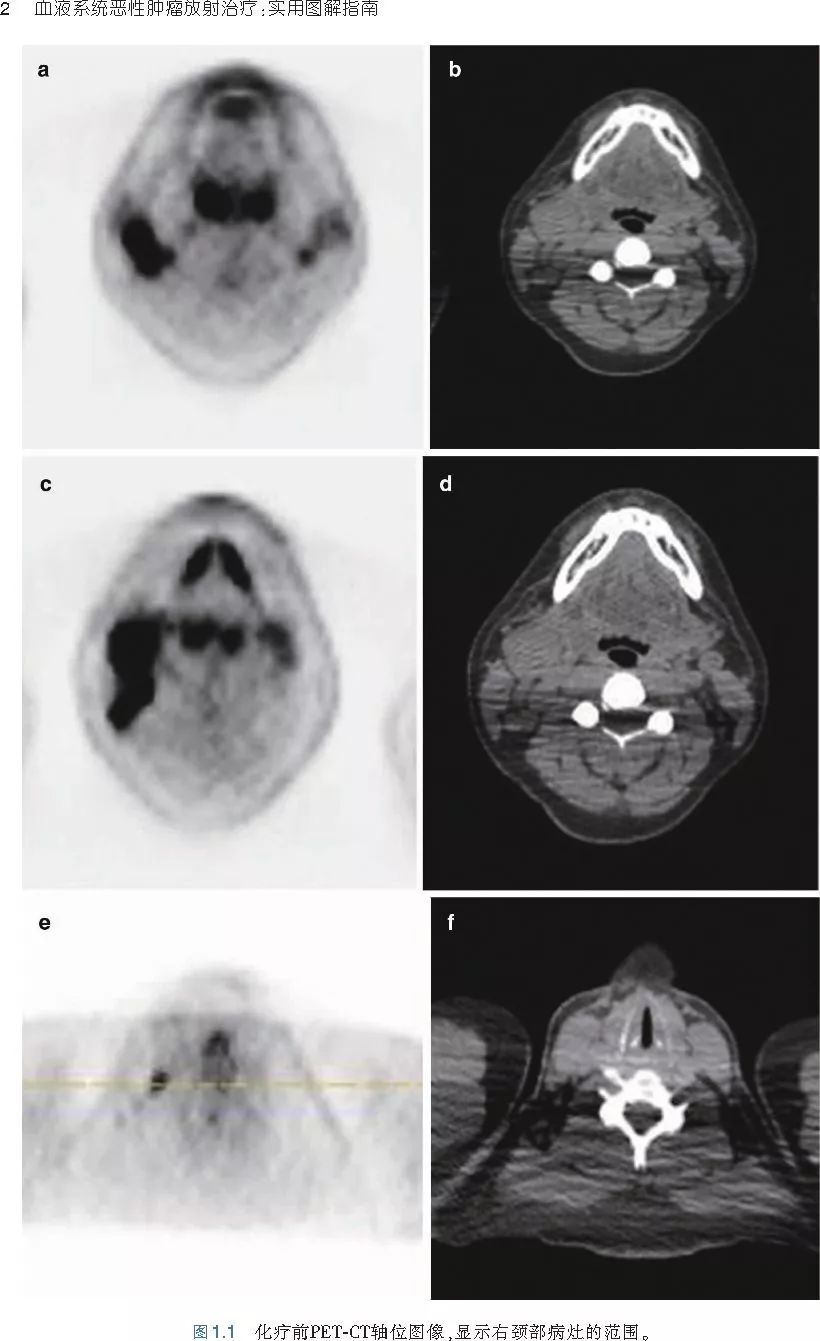

❤ 展开疾病诊断、病理描述及治疗方向的详细阐述,包含医学影像,图文并茂,深入浅出。

本书案例讨论遵循标准格式,包括临床描述,其次是与诊断相关的病理描述和分期,然后详细讨论治疗选择。最后,确定治疗方案,并提供所使用的规划放疗技术/方式的图像。对放射肿瘤医生进行临床决策非常有帮助,对于血液病临床医生也有很好的指导作用。